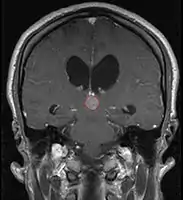

Pineal Gland Tumors

- Work-up includes MRI, CSF, serum markers for bHCG and AFP

- Usually well-circumscribed, large lesions, sometimes with cystic component